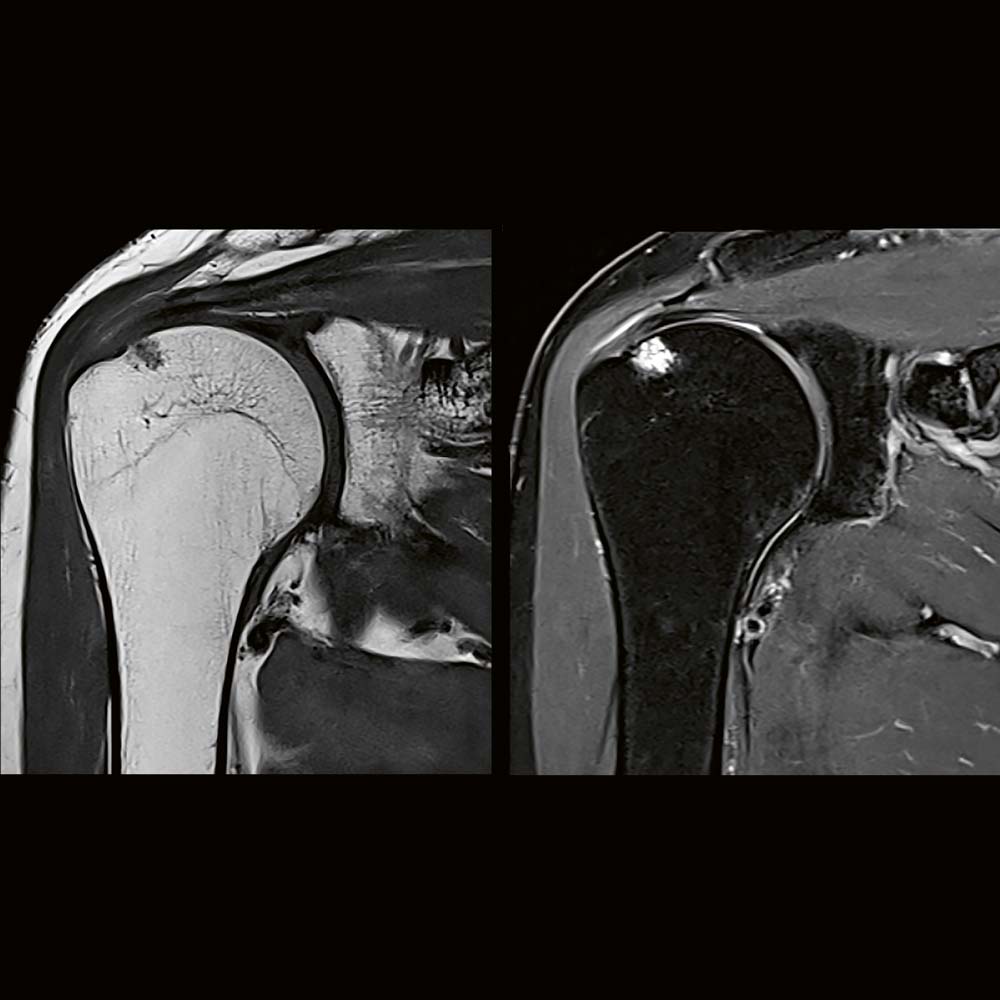

Zespół bolesnego barku

Zespół bolesnego barku to powszechnie występujące schorzenie układu mięśniowo-szkieletowego, dotykające zarówno osoby aktywne fizycznie, jak i prowadzone siedzący tryb życia. Objawia się bólem barku, nasilającym się zwłaszcza przy unoszeniu ręki ponad głowę, a w bardziej zaawansowanych przypadkach prowadzi do poważnych ograniczeń ruchomości. Choć na pierwszy rzut oka może wydawać się błahym problemem, nieleczony zespół bolesnego […]